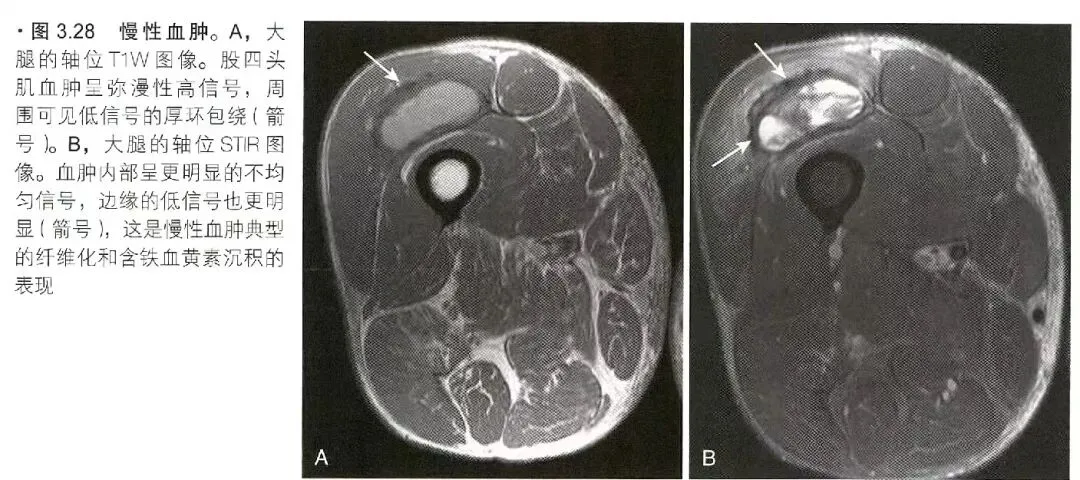

肌肉创伤

肌肉创伤可分为间接肌肉损伤、直接肌肉损伤和其它肌肉损伤。